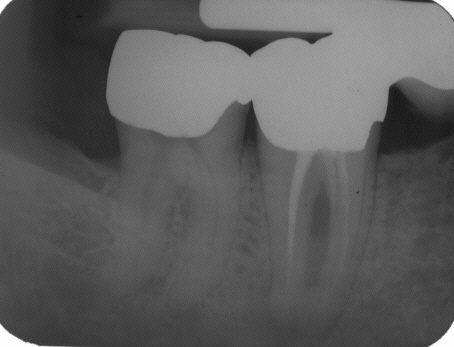

Abschlusskontrolle der WF

Abschlusskontrolle der WF im Oktober 2002. Man beachte die dreidimensionale Füllung des apikalen Deltas des distalen Kanalsystems (hier konnte Patency etabliert werden) sowie die Füllung der Seitenkanäle im Bereich der Furkation, auf deren Höhe sich auch der lingualen Abszeß befand.